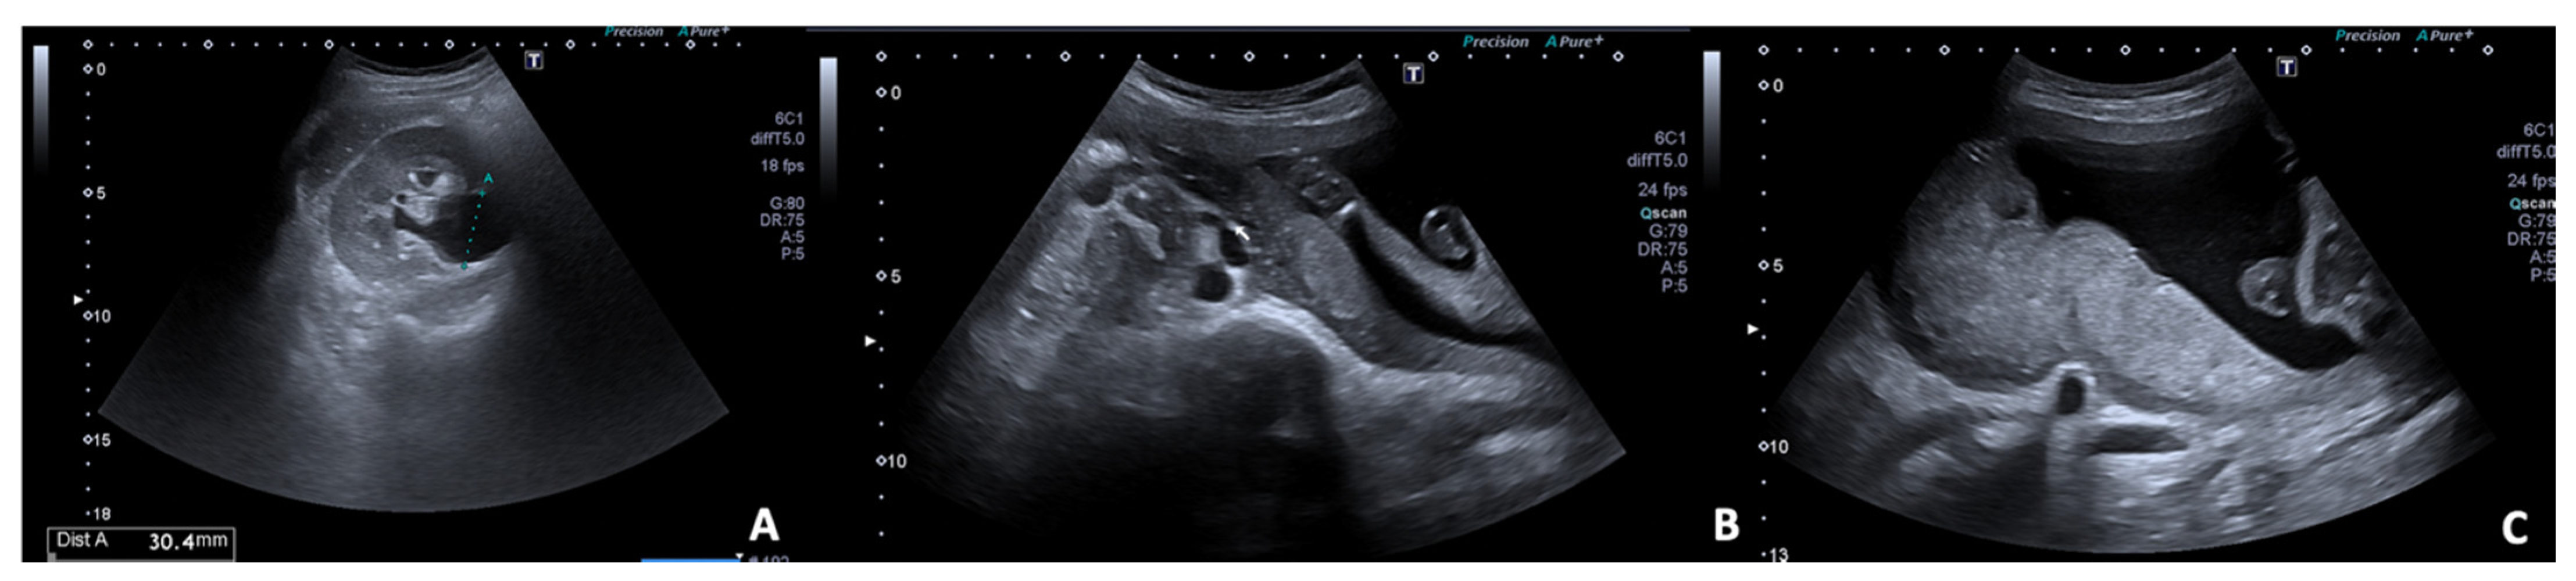

5.1. Appendicitis

- Giljaca, V.; Nadarevic, T.; Poropat, G.; Nadarevic, V.S.; Stimac, D. Diagnostic Accuracy of Abdominal Ultrasound for Diagnosis of Acute Appendicitis: Systematic Review and Meta-analysis. World J. Surg. 2017, 41, 693–700. [Google Scholar] [CrossRef] [PubMed]

- Pedrosa, I.; Levine, D.; Eyvazzadeh, A.D.; Siewert, B.; Ngo, L.; Rofsky, N.M. MR Imaging Evaluation of Acute Appendicitis in Pregnancy. Radiology 2006, 238, 891–899. [Google Scholar] [CrossRef] [PubMed]

- Poletti, P.-A.; Botsikas, D.; Becker, M.; Picarra, M.; Rutschmann, O.T.; Buchs, N.C.; Zaidi, H.; Platon, A. Suspicion of appendicitis in pregnant women: Emergency evaluation by sonography and low-dose CT with oral contrast. Eur. Radiol. 2019, 29, 345–352. [Google Scholar] [CrossRef]